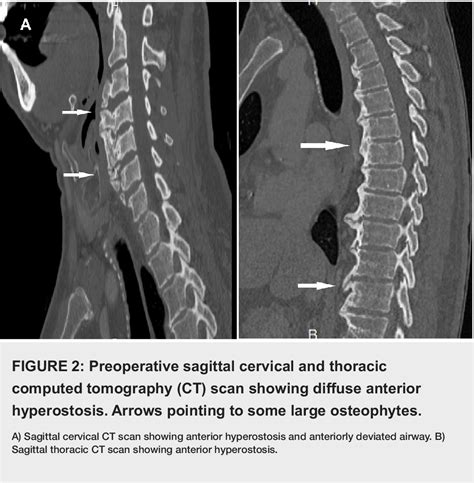

If you suspect that your symptoms are related to bone spurs, a healthcare professional will perform a physical examination to test your reflexes, muscle strength, and range of motion. To confirm the diagnosis of osteophytes in cervical vertebrae, imaging is typically required.

• X-rays: Highly effective at visualizing the bony projections and narrowing of the disc space.

• MRI (Magnetic Resonance Imaging): Provides detailed images of soft tissues, nerves, and the spinal cord, allowing doctors to see if the bone spurs are compressing neural structures.

• CT Scans: Used when more detailed bony imaging is required than what an X-ray can provide.